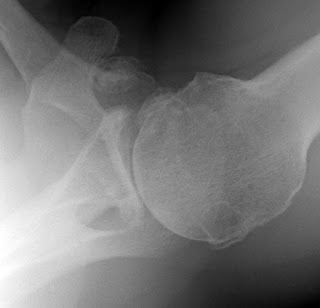

The second key view is the axillary view taken with the arm in the functional position of elevation in the plane of the scapula and oriented so that both the spinoglenoid notch and the scapular neck are visible. This view shows a different perspective of the humeral anatomy, the amount of glenoid bone, the shape of the glenoid, its version in relation to the plane of the scapula and the relationship of the humeral head to the glenoid fossa. We have named the axillary view taken in with the arm elevated in the plane of the scapula the ‘truth’ view. This is because it demonstrates the glenohumeral relationships in the functional position of elevation; this is in contrast to CT scans, which have the disadvantage of being taken with the arm in the adducted position

Unfortunately, many of the ‘axillary views’ sent to us on patients for consultation are taken without standardization, making it impossible to determine the important features of the glenohumeral joint as shown below.

Since arthritis usually involves the central aspect of the humeral head,

joint space narrowing is most evident on the truth view as opposed to images made with the arm at the side. Of even greater importance is the ability of the axillary ‘truth’ view to show posterior subluxation or ‘functional decentering’ that is not evident in images taken with the arm at the side.

The degree of posterior subluxation can be measured as (a) the position of the center of the humeral head in relation to the plane of the scapula, (b) the position of the center of the humeral head in relation to the glenoid face or (c) the point of contact of the humeral articular surface on the glenoid articular surface. We prefer the latter because it is this point of contact that reflects the degree of centering of the net humeral joint reaction force on the glenoid. It is the malcentering of this joint reaction force that leads to posterior instability, posterior glenoid wear and to rocking horse loosening of prosthetic glenoid components. The standardized axillary view also enables the surgeon to see the shape of the glenoid surface. Three main types have been described: concentric wear (type A)

In actual practice, there are so many intermediate types of glenoid pathoanatomy that rigorous separation into a few distinct classes is difficult.

An important aspect of glenoid pathology is the amount of the glenoid that is involved in the pathologic concavity, known as the ‘neoglenoid. Finally, the standardized axillary view enables the measurement of the degree of glenoid retroversion in relation to the body of the scapula. Thus, on the standardized axillary view, the surgeon can usually determine the major important characteristics of glenohumeral arthritic pathoanatomy: the amount of joint space narrowing, the degree of retroversion, the degree of posterior subluxation with the arm in a functional position, the glenoid shape, the percentage of the glenoid involved in the pathologic concavity and the angle of retroversion.